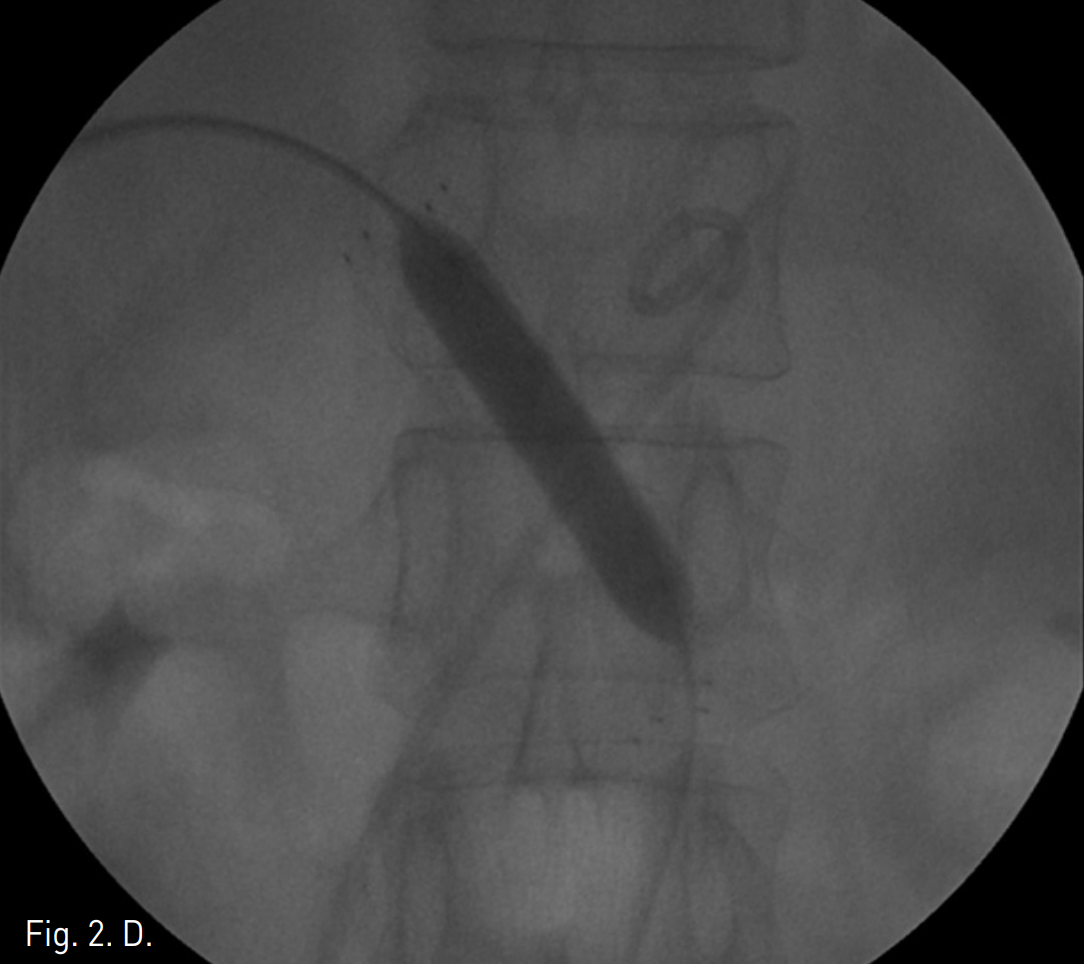

조영증강 복부 CT에서 췌장 경부 상부에 침윤성의 연부조직 음영이 보이며 3cm 정도 크기의 낭성병변이 동반되어 있음. 주문맥은 상기한 연부조직 음영으로 둘러싸여 있고 협착이 있음.주문맥 주위로 해면상변환 (cavernous transformation)이 보임(Fig 1).

Fig. 1

A-B. On CT, soft tissue densities are infiltrated around main portal vein and pancreas. Portal vein (arrow in A) is narrowed and many small collateral vessels (double arrow in B) are around main portal vein. There is about 3cm sized cystic mass close to infiltrative soft tissue densities (arrowhead in A).